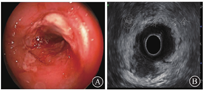

2021年4月19日完善小肠CT造影(computed tomography enterography,CTE)检查示降结肠与乙状结肠交界处可见节段性腔壁增厚、对称,管腔狭窄改变,并可见明显强化征象,未见明确分层和梳状征;所示空肠、回肠大部充盈扩张,未见明显腔壁增厚和管腔狭窄改变,未见明确异常强化征象;腹腔未见积气、积液(图2)。当日完善结肠镜+超声内镜检查,白光内镜下见直肠黏膜光滑,乙状结肠距肛门约20 cm以下可见多发不规则溃疡,伴自发性少量渗血,肠腔狭窄(图3A),无法通过,病灶处予多块深挖活检;超声内镜检查示乙状结肠局部肠壁增厚,最厚处约1.3 cm,肠壁层次结构模糊不清、呈较均匀低回声,浆膜层不完整,病变周围腹腔可见多发低回声区(图3B)。肠镜活检病理示乙状结肠黏膜表面糜烂,伴凝固性坏死,肠黏膜固有层内大量淋巴细胞增生,增生的淋巴细胞呈小到中等大小,可见异型细胞;免疫组织化学检查示增生的淋巴细胞以自然杀伤/T细胞为主,可见少量大B淋巴细胞,EB病毒编码区(Epstein-Barr encoding region,EBER)阳性,未见巨细胞病毒包涵体。

消化内科胡益群主任医师:本例患者存在腹痛、腹泻,结肠节段性溃疡,外院活检病理结果提示炎症改变,肿瘤标志物不高,容易引导临床医师拟诊为克罗恩病。我国克罗恩病的发病高峰年龄为18~35岁[8],本例患者年龄偏大。实际上,结肠溃疡变化多样,相似的表现可能有不同的病因。超声内镜有助于观察组织层次和周围结构的改变,能比白光内镜提供更多的辅助诊断信息。患者行结肠超声内镜检查,提示局部乙状结肠壁全层增厚,正常层次消失,表现为较均匀的低回声改变,符合淋巴瘤的超声表现。克罗恩病在超声内镜下也可表现为肠壁增厚,层次不清,可见低回声改变,但本例患者无典型克罗恩病的内镜或病理改变,结合CTE结果,考虑克罗恩病诊断不成立。腹痛是淋巴瘤患者最常见的主诉,许多患者往往因可疑炎症性肠病或急腹症入院治疗[9],与患者既往诊治经过相似。最终确诊需依赖病理学检查结果。